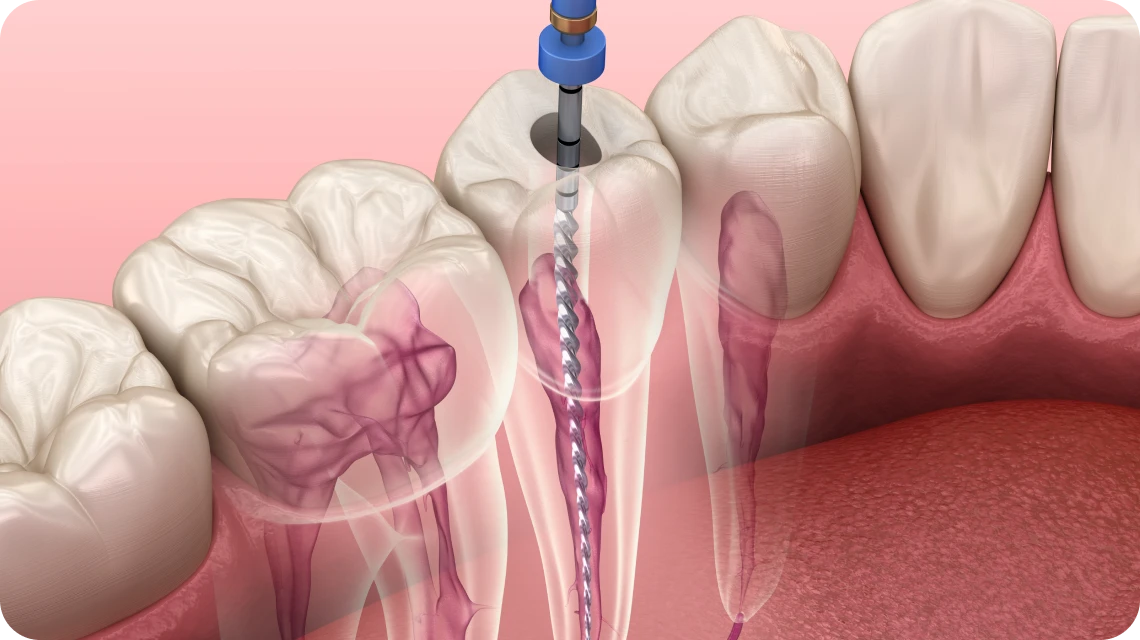

L’endodontie est une spécialité dentaire qui se concentre sur le traitement des infections à l’intérieur des dents, notamment des canaux radiculaires. Lorsqu’une carie profonde ou un traumatisme atteint la pulpe dentaire, un traitement endodontique est nécessaire pour éliminer l’infection et préserver la dent. Le traitement consiste à nettoyer et désinfecter les canaux, puis à les obturer pour éviter toute réinfection.

L’endodontie consiste à soigner l’intérieur de la dent, notamment le canal radiculaire, pour éliminer l’infection et soulager la douleur, tout en conservant la dent naturelle.

Dévitalisation dentaire

Cette procédure est réalisée lorsque la dent est trop endommagée ou infectée pour être sauvée par des méthodes plus conservatrices.